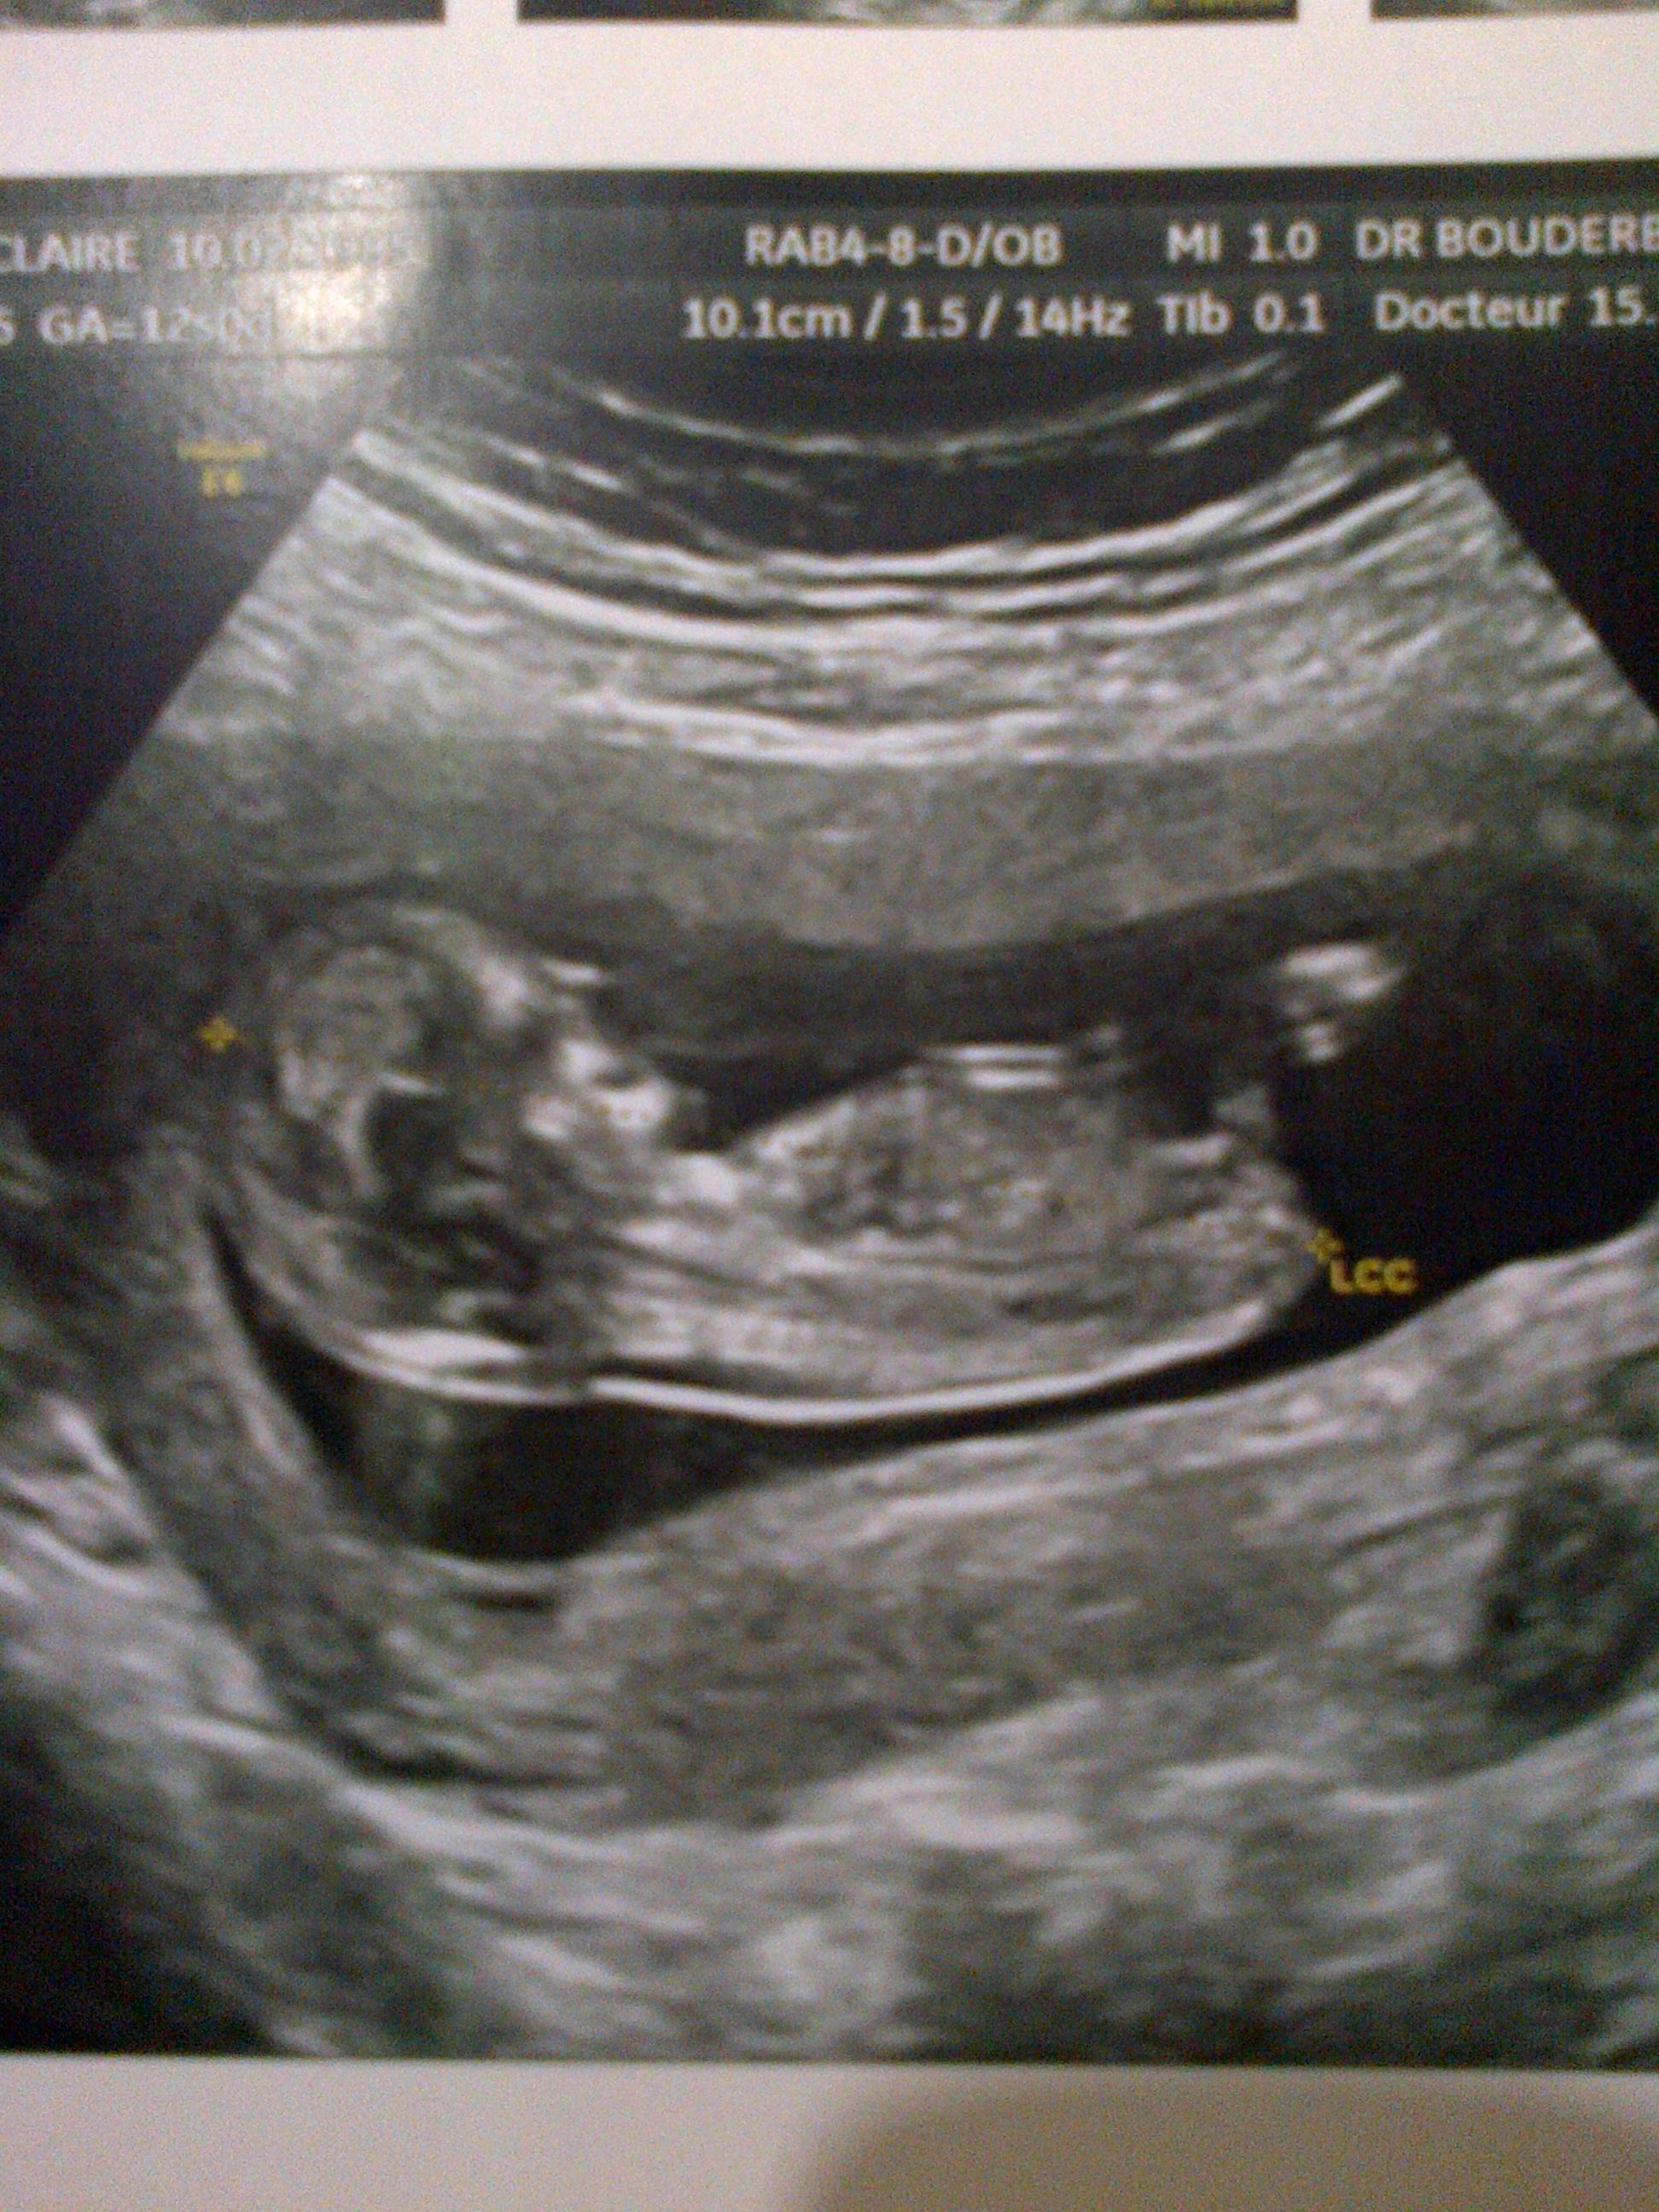

Moi j'ai une echo qui y ressemble on pourrait faire des pronostics si vous voulez mais regerdez bien les liens...

Si tu veux met ton écho je vais essayer de voir

je vais faire ça alors!

Pièces jointes

• 618-2274.jpg

618-2274.jpg

1.1 MB · Affichages: 96